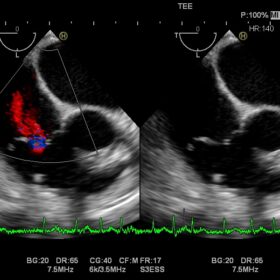

Cardio 2D, Color, PW, CW and TDI mode

The Ultra BE, an ultrasound-specific digital signal processor is at the core of the Noblus. Achieving advanced beam formation and sophisticated image processing. Migrated from the high-end HI VISION cart-based systems, this technology brings reliable diagnostic performance. That will ensure a smooth workflow. It’s powerful transmission and reception capability enables functions. Such as Real-time Tissue Elastography (RTE) and dynamic Contrast Harmonic Imaging (dCHI), modalities that can offer increased diagnostic confidence.

The Noblus offers premium modalities that can be exploited in many different clinical situations. Although compact in design, the powerful engine of the Noblus enables functions such as Real-time Tissue Elastography (RTE), dynamic Contrast Harmonic Imaging (dCHI), real-time 3D with STIC (Spatio-temporal Image Correlation) option and CW Doppler, features previously found only on larger cart-based systems.